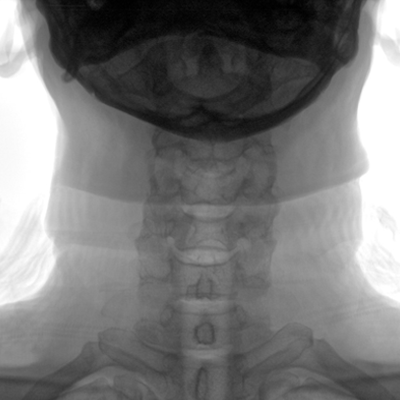

大尺寸動態(tài)平板探測器,高DQE、低噪聲、圖像清晰。采用多分辨率圖像增強處理技術(shù),不同部位不同圖像處理算法,滿足客戶多樣化的需求。

采用智能變頻脈沖透視技術(shù),優(yōu)化圖像質(zhì)量的同時降低輻射劑量,呵護(hù)醫(yī)患健康